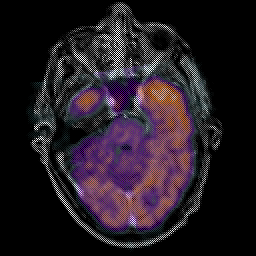

Glioma Overlay -- Slice #6

[Home][Help][Clinical] Slice 6